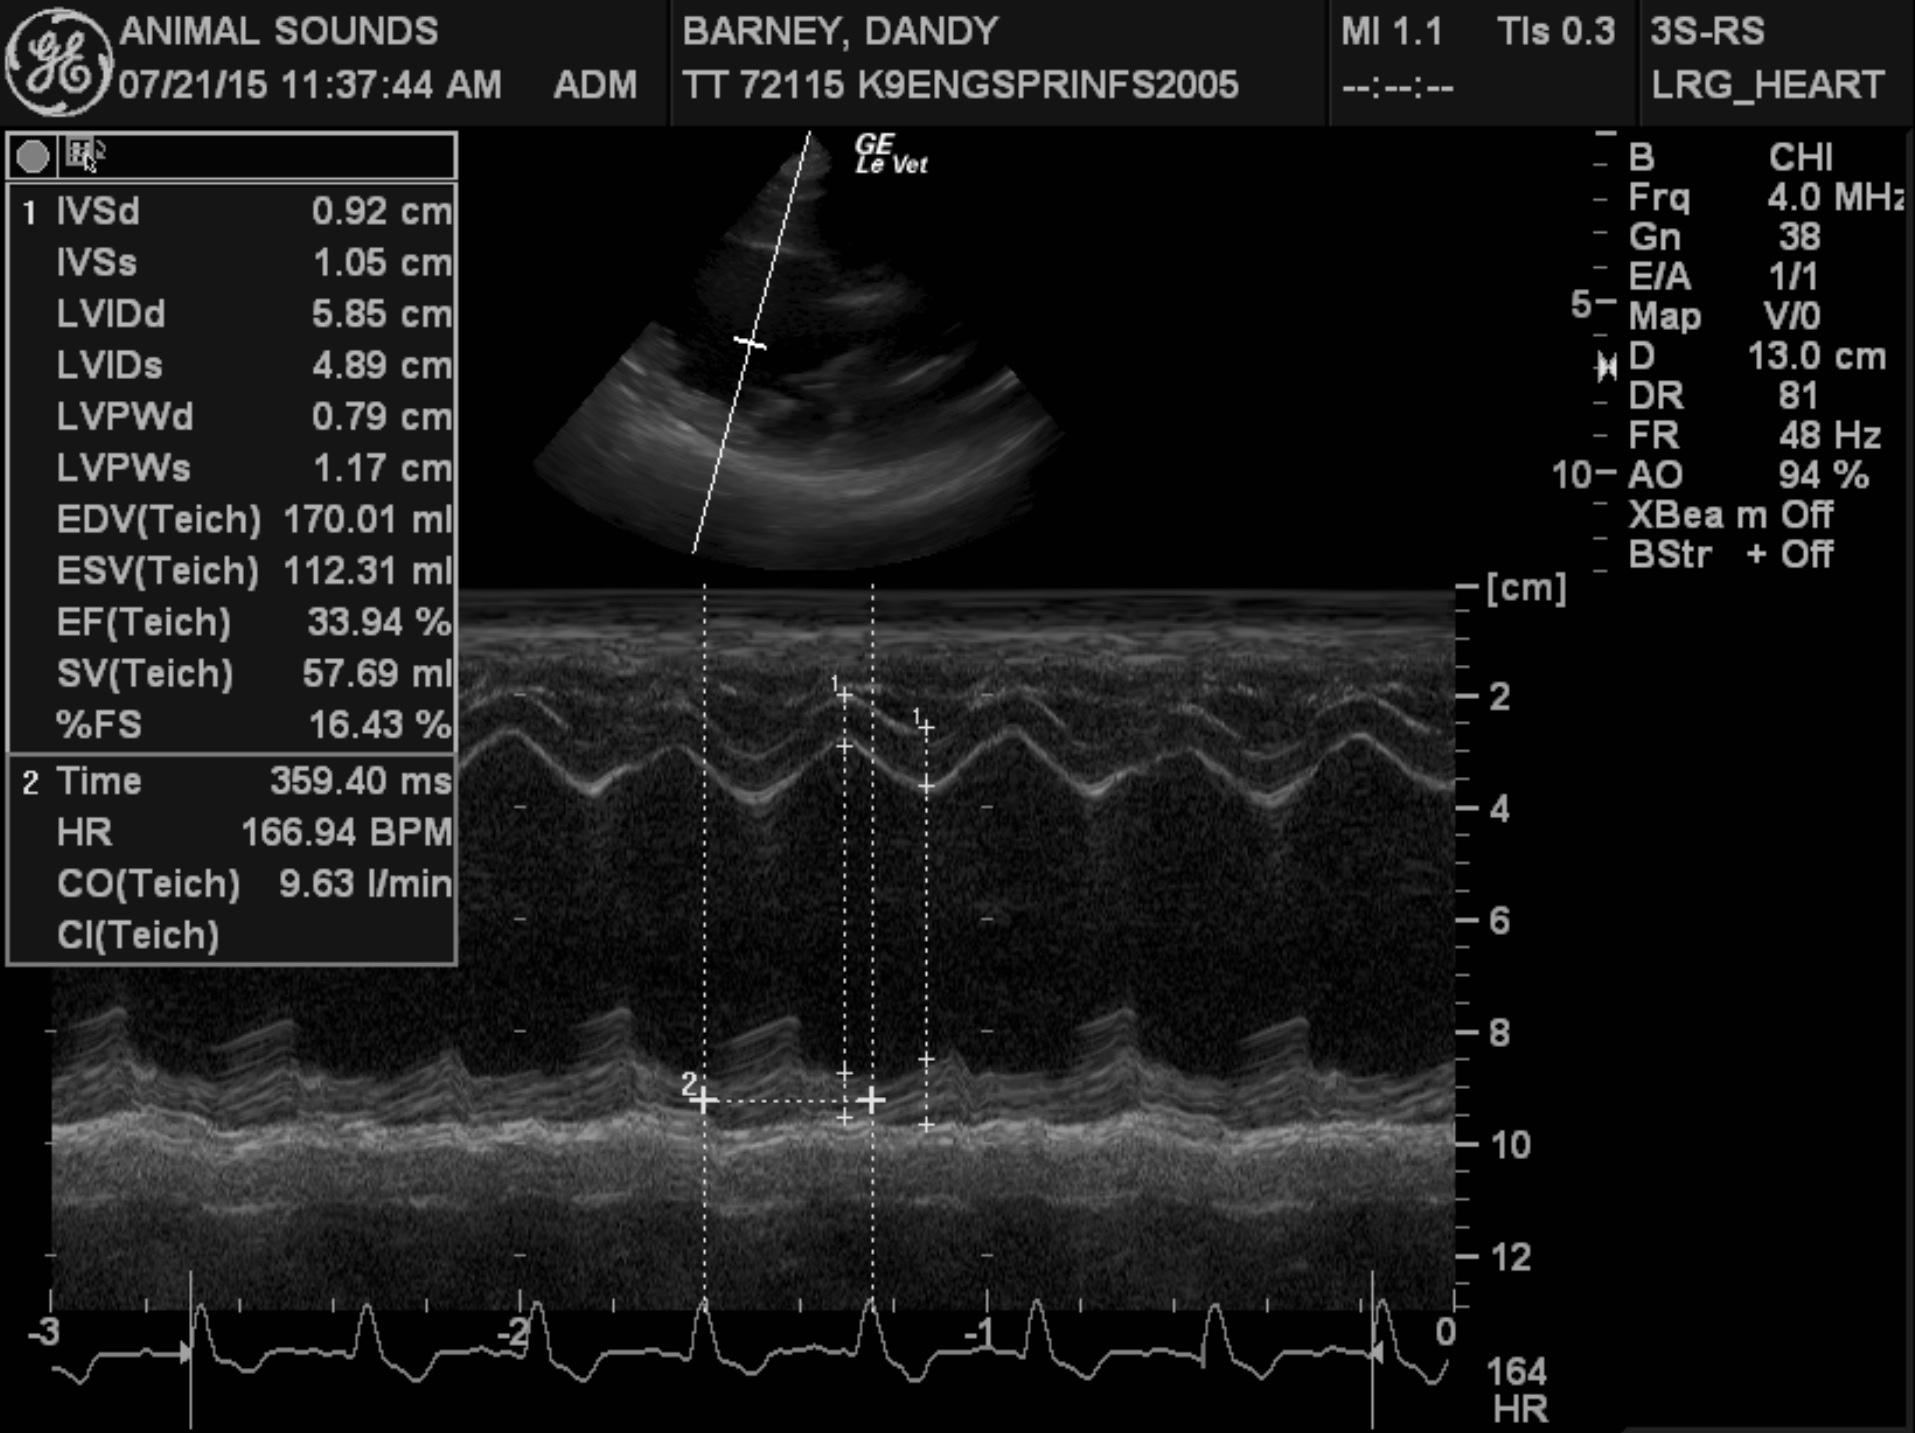

Echocardiogram findings: There is moderate to severe left ventricular dilation. The mitral valve appears normal, though a mild jet of central mitral regurgitation is present. Left ventricular systolic function is globally depressed. The aorta and aortic valve are normal. Right atrial and right ventricular dimensions are normal. The tricuspid valve appears normal, though trace physiologic tricuspid regurgitation is present. The pulmonary artery and pulmonic valve are normal. No pericardial effusion or cardiac masses are seen.

LA – 57.8 mm

LVIDd – 66.2 mm

LVIDs – 54.5 mm

FS – 17.6%

This examination demonstrates global left ventricular systolic dysfunction, consistent with dilated cardiomyopathy. Secondary to the patient’s myocardial dysfunction, she has severe left ventricular dilation, as well as moderate to severe left atrial dilation, and it appears that she is in mild congestive heart failure based on her thoracic radiographic findings. Given the severity of her cardiac disease, it appears very likely that this is the cause of her arrhythmia.